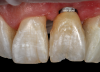

(35.) An implant being inserted into the prepared osteotomy of a patient who presented for the replacement of the maxillary left central incisor.

Figure 35

(36.) The implant’s primary stability was assessed by RFA, and the ISQ value greater than 65 was used to determine that immediate provisionalization was indicated.

Figure 36

(37.) The implant’s primary stability was assessed by RFA, and the ISQ value greater than 65 was used to determine that immediate provisionalization was indicated.

Figure 37